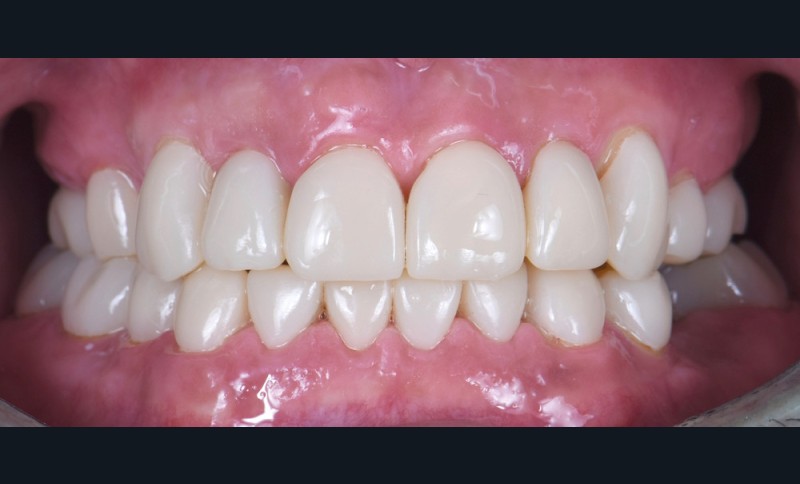

Au vu du contexte para-fonctionnel et de l’étendue de la perte tissulaire, des coiffes périphériques minimalement invasives ont été choisies afin de restaurer l’esthétique et la fonction. Actuellement, aucun consensus n’est fait sur le choix du matériau d’infrastructure à privilégier. Les matériaux hybrides usinables présentent des propriétés mécaniques, physiques et biologiques intéressantes en contexte d’usure sévère (e.g., module d’élasticité, résistance à la propagation de fêlures, facilité de réintervention). Une réhabilitation globale avec remontée de dimension verticale d’occlusion (DVO) par l’intermédiaire de coiffes composites renforcés en nano-céramiques est décrite.

Les auteurs remercient le laboratoire Bertin, Bordeaux, ainsi que Madame Delphine Bibard pour leur précieuse aide dans la réalisation de ce cas.